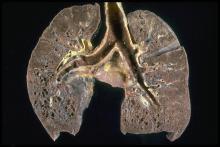

病理图像显示出结节病蜂窝状改变:伴随突出的蜂窝中下叶使上肺纤维化和一些蜂窝状改变。蜂窝由囊状扩张气道瘢痕组织构成,类似蜂窝的形状。它是一种非特异性的多种类型构成的间质性肺疾病的终末期。

本病可自行缓解或转为慢性疾病、反复发作和经治疗后缓解。有报导称,在5年随访的病例中,34%的患者完全康复,30%的患者改善,20%基本不变,8%病情恶化,另有8%的患者因发生肺的广泛纤维化等原因而导致死亡。 也有报导称,大约有一半的患者能够在12-36个月内或者最多五年时间,在完全没有治疗或者经过治疗的情况下治愈。 当心脏受累时,预后较差。 结节病的患者患癌症的风险显着增加,尤其是肺癌、恶性淋巴瘤 和一些影响其他器官的结节病的其它类型癌症。 在结节病-淋巴瘤综合征中,结节病常导致淋巴组织增生疾病,如非霍奇金淋巴瘤。 原因可以归纳于结节病的发病过程中所发生的潜在免疫系统异常。 结节病也可以继发于癌症 或同时与癌症发生。 报道称毛细胞白血病、 急性骨髓性白血病 与急性粒细胞性白血病 都与结节病有关。